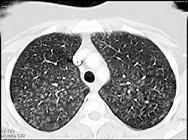

问题 男性,50岁,反复干咳、进行性气促2个月,加重5天。无发热,无咯血,抗感染治疗效果欠佳。胸部CT见图。支气管肺泡灌洗液PAS染色阳性。最有效的治疗是 ( )

选项 A.抗肿瘤治疗 B.糖皮质激素 C.抗生素 D.支气管肺泡灌洗 E.抗心衰治疗

答案 D